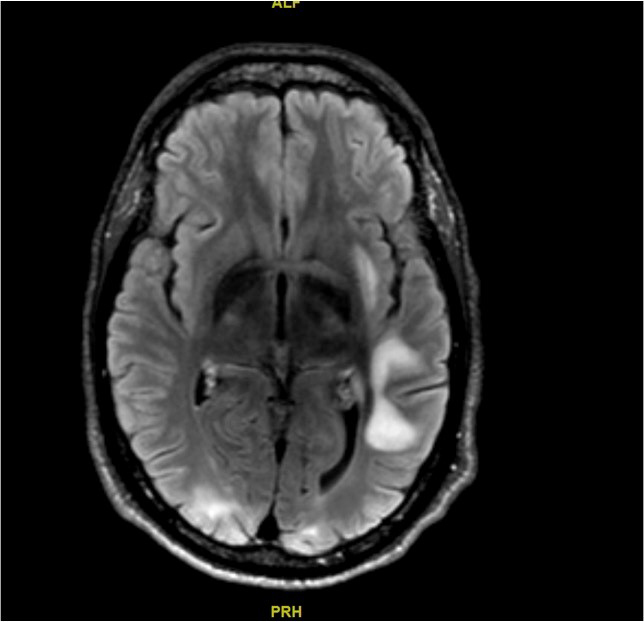

Une IRM est alors réalisée (coupe T2 FLAIR axiales) (images ci-dessous) : Les coupes T1 montrent des lésions hypo-intenses des mêmes territoires, mais aucune lésion ne prend le contraste.

Question 11 - Quel(s) est(sont) le(s) diagnostic(s) retenu(s) à ce stade ?

LEMP : hypo-T1 hyperT2, pas de prise de contraste.

Vous retenez le diagnostic de leucoencéphalopathie multifocale progressive.